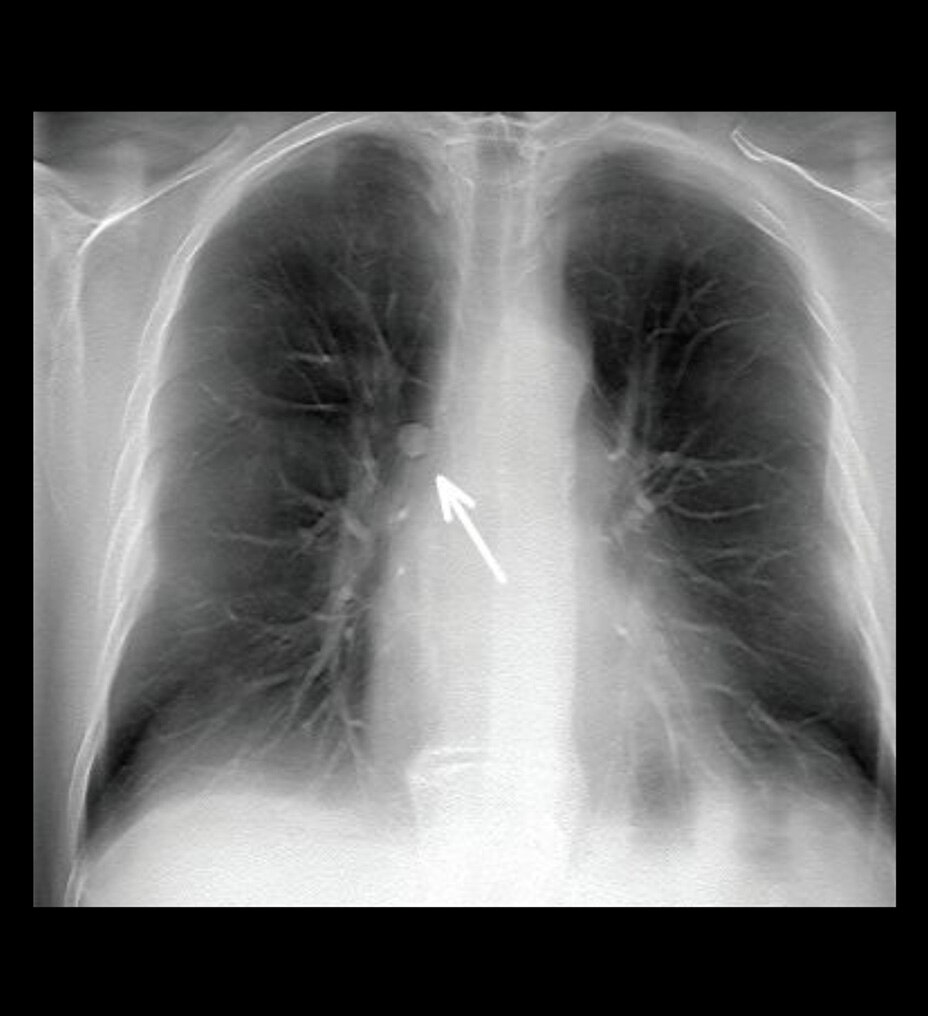

Calidad de imagen excepcional con AIR™ Recon DL

Las imágenes más claras le permitirán diagnosticar de forma más sencilla, y, gracias a nuestra tecnología de aprendizaje profundo líder en el sector, AIR™ Recon DL le ayudará a obtener imágenes excepcionales más rápido. Revoluciona la forma de visualizar las imágenes de RM, garantizando los resultados más nítidos en una amplia variedad de anatomías. Además, le permite tener más confianza en las imágenes adquiridas, con exámenes fáciles de interpretar y de alta calidad que también pueden reducir la fatiga ocular y mejorar la experiencia general de los informes.